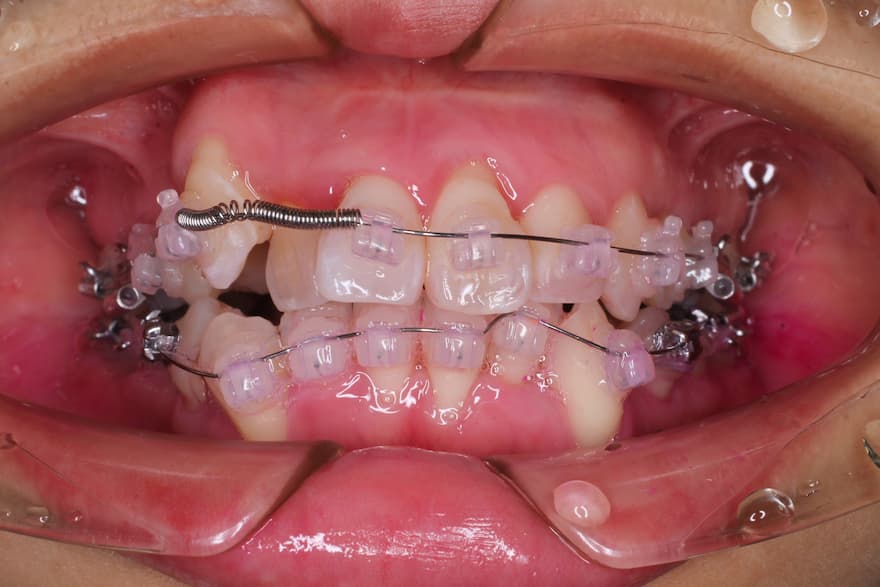

ブラケット装着